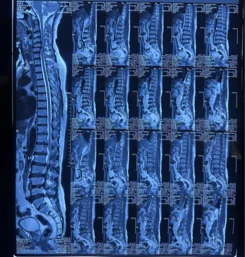

Before & After Clinical Gallery

We showcase real patient cases (with consent), including:

• Pre- and Post-operative MRIs and X-rays

• Disc Herniations, Stenosis, and Spondylolisthesis cases

• Visible improvement in alignment and decompression

Before

After